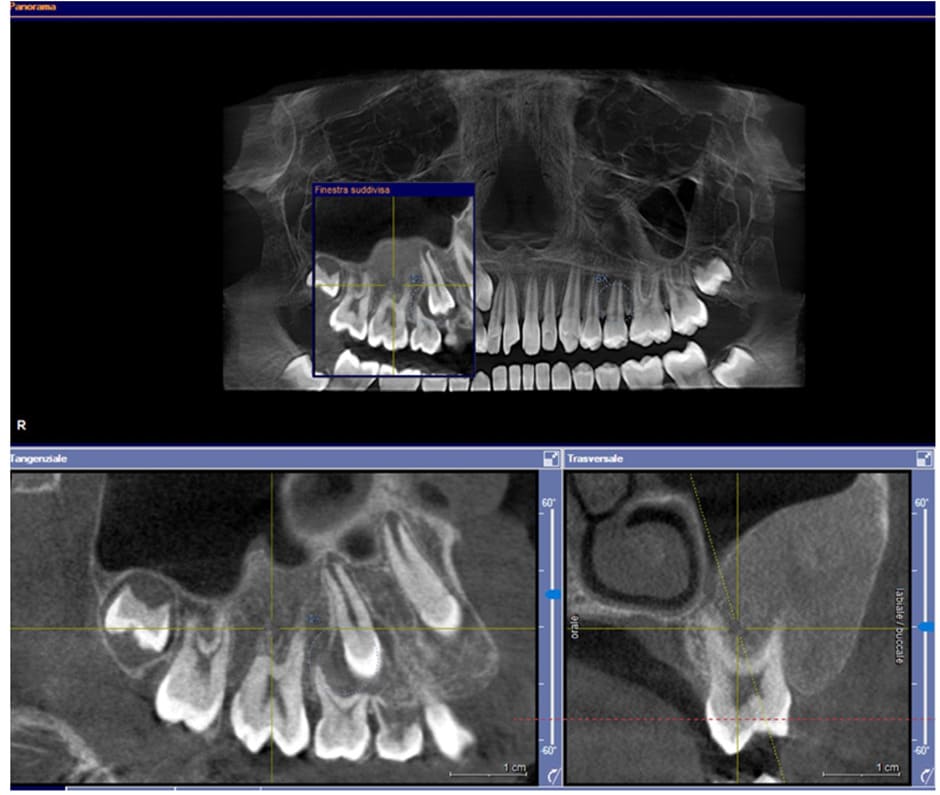

Case 1: a 12-year-old male patient from Catanzaro, Italy, was referred to the Odontostomatology Department of Galliera Hospital in Genoa, Italy. The patient presented an expansive mass involving the right upper jaw (Fig. 2) and retained right permanent upper canine. Upon clinical examination, the patient exhibited a hard lesion causing altered eruption of the dental element 1.3, a lack of space in the dental arch, subsequent to the exfoliation of the deciduous canine, and a buccal protuberance of the permanent canine, in close proximity to the lateral incisor root. Initial bidimensional radiographic examination (OPT) revealed a ground-glass opacity within the right maxillary sinus and malposition of the permanent canine. To delineate the lesion in three dimensions and to locate the right upper canine accurately, cone-beam computed tomography (CBC, Fig. 1) was necessary. The CBCT depicted the buccal position of the canine and defined the borders of the fibro- osseous lesion, which also involved the buccal aspect of the posterior elements, leading to altered passive eruption.

Figure1: Pre-operative CBCT scan.